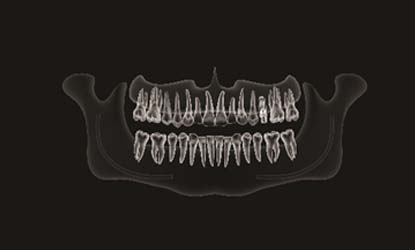

Problema: Trūksta krūminio danties

Tikslas:

Pakeisti trūkstamą dantį dantų implantu

Rezultatas:

Atkurta pilnavertė kramtymo funkciją